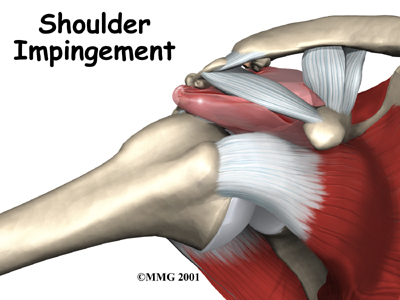

Many people refer to any pain in the shoulder as bursitis. The term bursitis really only means that the part of the shoulder called the bursa is inflamed. Tendonitis is when a tendon gets inflamed. This can be another source of pain in the shoulder. Many different problems can cause inflammation of the bursa or tendons. Impingement syndrome is one of those problems. Impingement syndrome occurs when the rotator cuff tendons rub against the roof of the shoulder, the acromion.

Usually, there is enough room between the acromion and the rotator cuff so that the tendons slide easily underneath the acromion as the arm is raised. But each time you raise your arm, there is a bit of rubbing or pinching on the tendons and the bursa. This rubbing or pinching action is called impingement.

Impingement occurs to some degree in everyone's shoulder. Day-to-day activities that involve using the arm above shoulder level cause some impingement. Usually it doesn't lead to any prolonged pain. But having poor posture, continuously working with the arms raised overhead, repeated throwing activities, or other repetitive actions of the shoulder can cause impingement to become a problem. Impingement becomes a problem when it causes irritation or damage to the rotator cuff tendons.

Raising the arm tends to force the humerus against the edge of the acromion. With overuse, this can cause irritation and swelling of the bursa. If any other condition decreases the amount of space between the acromion and the rotator cuff tendons, the impingement may get worse. For example, poor posture that involves an increased forward curve in the upper back (kyphosis) and rolling inward of the shoulders affects the alignment of the humerus under the acromion. This alters the biomechanics of the shoulder (the ability of the shoulder to move freely and effeciently in space) which means even daily activity such as reaching increases the contact under the acromion.